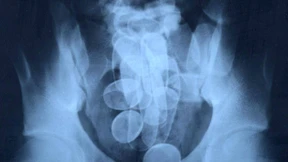

Frankfurter Zollbeamte haben mit Hilfe eines Drogenspürhundes zwei Kilogramm Kokain entdeckt. Dabei hat der mutmaßliche Drogenkurier das Rauschgift an einem ungewöhnlichen Ort versteckt.